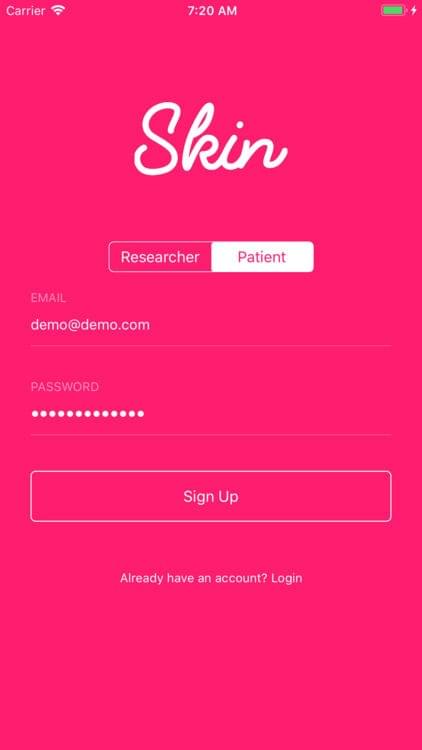

Skin — Secure Login

Skin is a digital health imaging app for tracking of moles and skin lesions. The platform is targeted towards academic researchers, physicians and patients looking to integrate a robust sharing platform for the management and surveillance of dermatological conditions. This app gives medical institutions and physicians a secure option to create scalable studies with hundreds of patient participants. The tool is intended to help support the creation of an intelligent model for the accurate diagnosis of skin diseases.